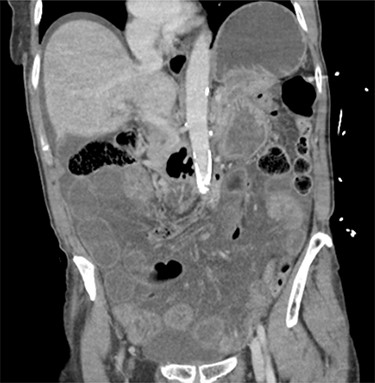

On examination she was mildly tachypnoeic, with normal oxygen saturations, heart rate was 74/min, with a blood pressure of 151/80 mmHg. On palpation, she was grossly distended, guarding and peritonitic throughout with no palpable hernias. Blood tests revealed an elevated white cell count of 13.4 × 109/l and a lactate of 2.3 mmol/l. An urgent computerized tomography (CT) scan of the abdomen and pelvis was performed. The CT demonstrated a large volume of free intraperitoneal fluid, with multiple loops of distended small bowel (Figs 1 and 2) without pneumoperitoneum. Although not noted in the report, there was concern about a ‘swirl’ in the mesentery, raising the possibility of a small bowel volvulus (SBV).

The patients CT scan, axial slice showing distended loops of small bowel and free fluid.